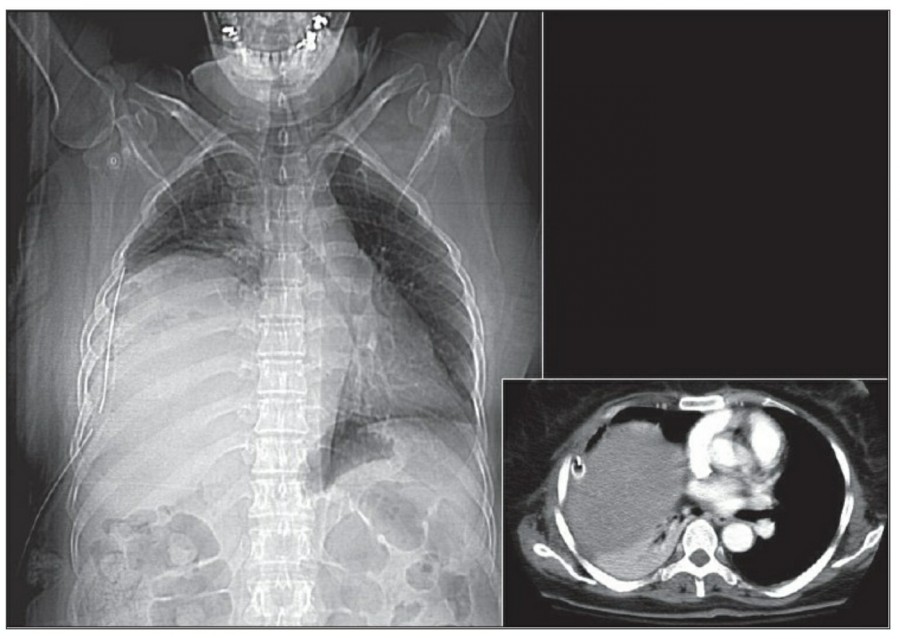

Pneumomediastinum은 mediastinum 안에 공기가 있는 경우를 일컬으며, intubation된 환자에서 구심적으로(centripetally) pulmonary interstitial dissection이 일어나는 경우와 관련이 있다.

또한 Mediastitnal air는 major airway 손상으로 인한 leakage나 retroperitoneum으로부터 fascial plane을 따른 air dissection에 의해 발생하기도 한다. Pneumomediastinum은 목까지 공기가 진행이 가능하고, pneumopericardium은 이와는 다르게 심장의 밑 부분으로 진행한다. Pneumomediastium은 일반적으로 무증상이지만, 간혹 청진 시 restrosternal crunch가 들릴 수 있다. Chest X ray상에서 공기가 major vessel 주변이나 SVC의 medial border, azygos vein에서 surrounding lucency로 보일 수 있다. 또한 aortic knuckle, descending aorta, pulmonary artery의 윤곽으로 나타날 수도 있다. Posteromedial pneumomediastinum은 주로 esophageal rupture의 결과로 나타날 수 있는데, praspinal costophrenic angle과 left diaphragm의 praietal pleural로 air dissection이 가능하다. 이 결과 V-sign of Naclerio라고 불리는 V-shaped lucency가 발생한다.